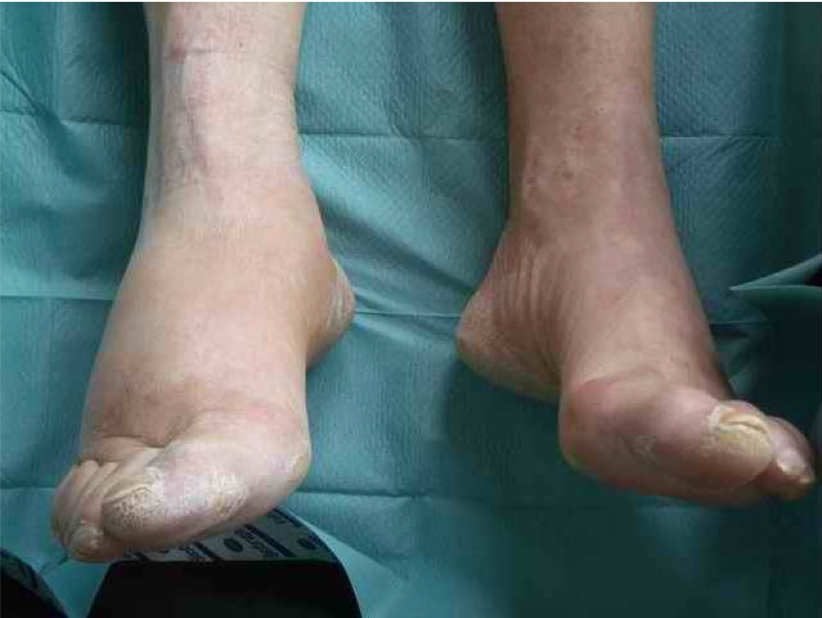

what is charcot foot?

Charcot foot is a condition causing weakening of the bones in the foot that can occur in people who have significant nerve damage (neuropathy)

The bones are weakened enough to fracture, and with continued walking, the foot eventually changes shape

All blood vessels in the foot under the ankle go haywire and the foot swells up and the bone goes spongy

Poorly understood

Can be triggered by trauma

Nothing you can do that helps it

End up with special moon boot things to alleviate pressure

Something that happens to the vasculature